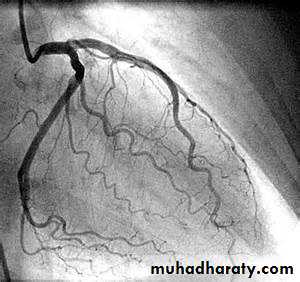

This involves passage of a reshaped catheter via a vein or artery into the heart under X-ray guidance, which allows the measurement of pressure and oxygen saturation in the cardiac chambers and great vessels, and the performance of angiograms by injecting contrast media into a chamber or blood vesselCoronary catheterization